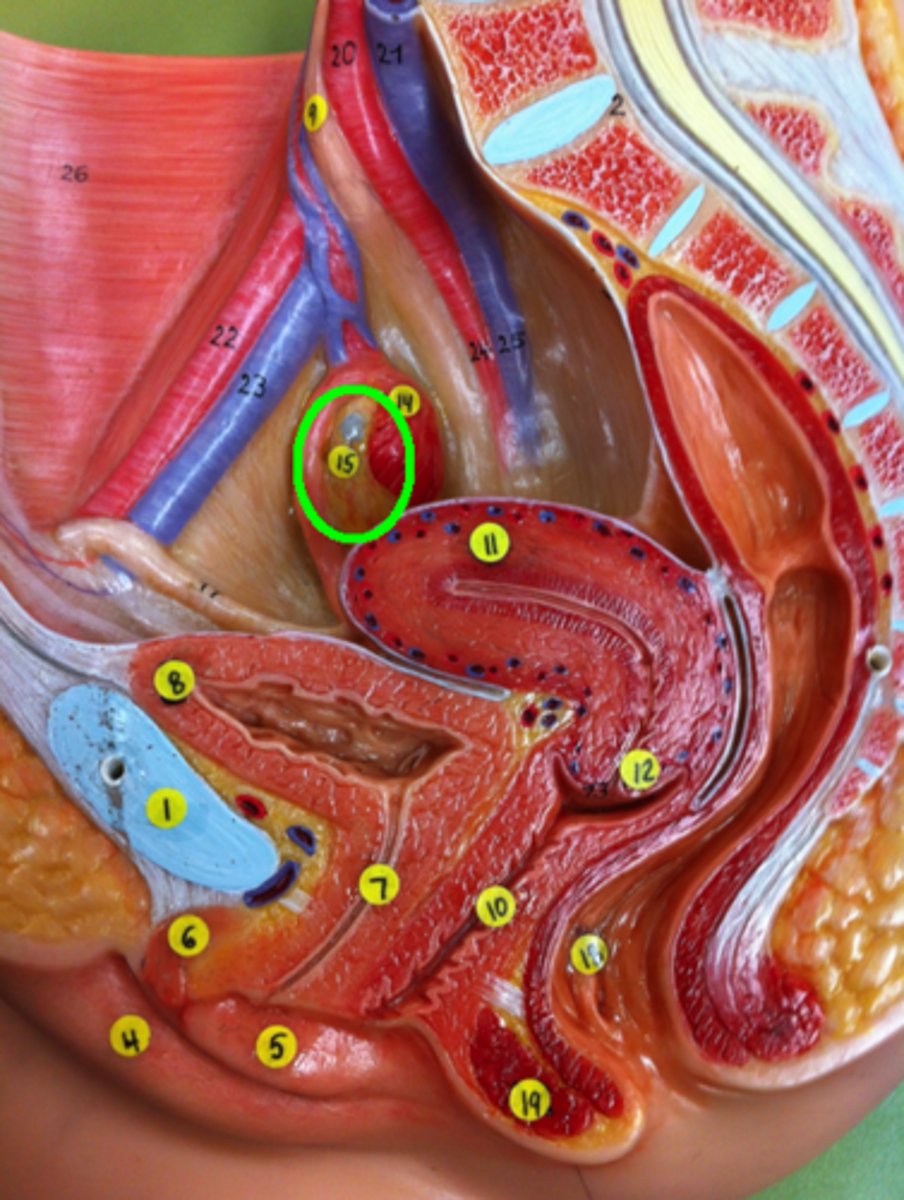

Pubic Bone

Labia Majora

Labia Minora

Clitoris

Urethra

Urinary Bladder

Ureter

Vagina

Uterus

Cervix of Uterus

Fimbriae of Uterine Tube

Ovary

Rectum

External Anal Sphincter